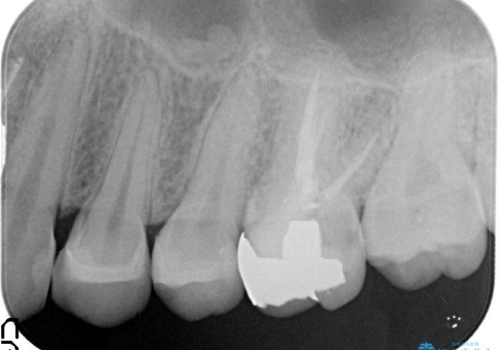

- 笑って見えるところの金属を白くしたいとのことで来院されました。

相談の結果、左上4,5のメタルインレーをセラミックインレーへと変更することとしました。

左上6は希望されなかったため、左上4,5のみをセラミックにやりかえています。